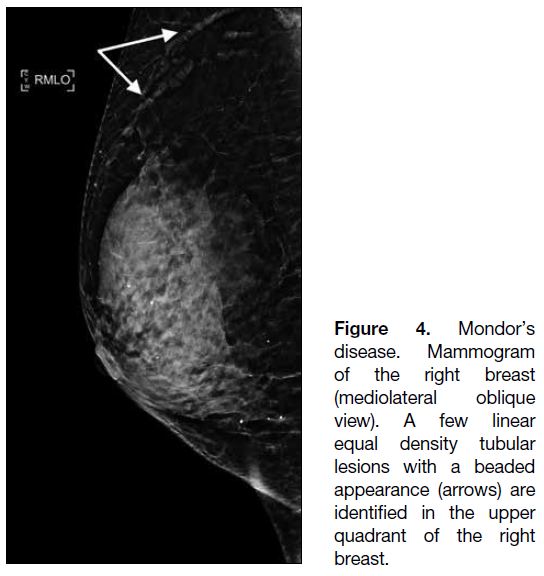

Mondor’s disease is a rare disease characterised by

inflammation and thrombosis of the superficial venous

structures in the breast. This disease is found in less

than 1% of the population.[5] Clinically, patients present

with skin swelling or tender cord-like palpable masses.

On mammography, elongated equal density tubular

structures are usually found in the upper outer quadrant

where the lateral thoracic veins are located (Figure 4).[6]

Ultrasound should be performed to exclude underlying

breast malignancy since dilated ducts could mimic

Mondor’s disease mammographically.[6]

Figure 4. Mondor’s

disease. Mammogram

of the right breast

(mediolateral oblique

view). A few linear

equal density tubular

lesions with a beaded

appearance (arrows) are

identified in the upper

quadrant of the right

breast.